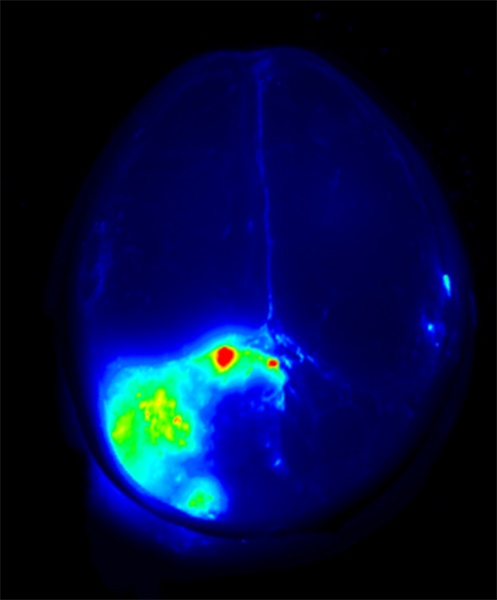

Harrington is one of a handful of surgeons across the country participating in a phase one trial of a “tumor paint” — a florescent dye that is attached to a peptide found in scorpion venom that mysteriously binds to cancerous cells, in theory lighting them up on scans and allowing surgeons to be better able to remove the cells during surgery.

Currently, the scorpion peptide is injected into the bloodstream during surgery so that the tissue removed during surgery can be examined to see how well the paint bound to cancer cells.

Currently, surgeons rely on scans to make educated guesses where the cancer cells are located, as they are invisible to the naked eye.